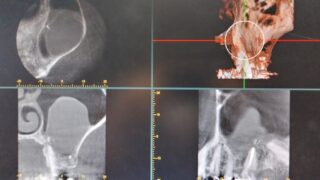

左側上顎洞内にうずら卵大の不透過像をみとめます。左側6は根管充填が実施されています。

左側6の根尖から連続して上顎洞粘膜が挙上されています。上顎洞病変の内部に根管治療材の一部迷入しています。今後残留していると病変に影響を与える可能性も否定できませんでし、病変の増大悪化考えられました。

左側上顎6の歯根は経上顎洞的に頬側根 口蓋根を切除しました。上顎洞内の嚢胞と嚢胞内の歯科材料異物は摘出されています。(術中CT)